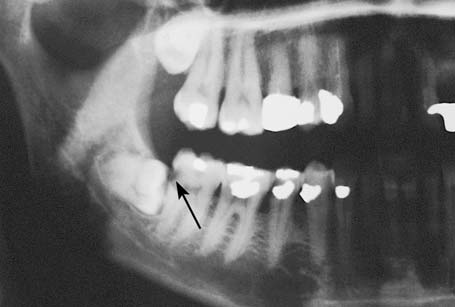

Impacted mandibular third molar with well-defined radiolucency at the distal area

The coexistence of an impacted tooth and various pathologic conditions is not an uncommon phenomenon. Often cystic lesions develop around the crown of the tooth and are depicted on the radiograph as different-sized radiolucencies. These cysts may be large and may displace the impacted tooth to any position in the jaw. Whenthe presence of such osteolytic lesions is verified radiographically, they must be removed together with the associated impacted tooth.